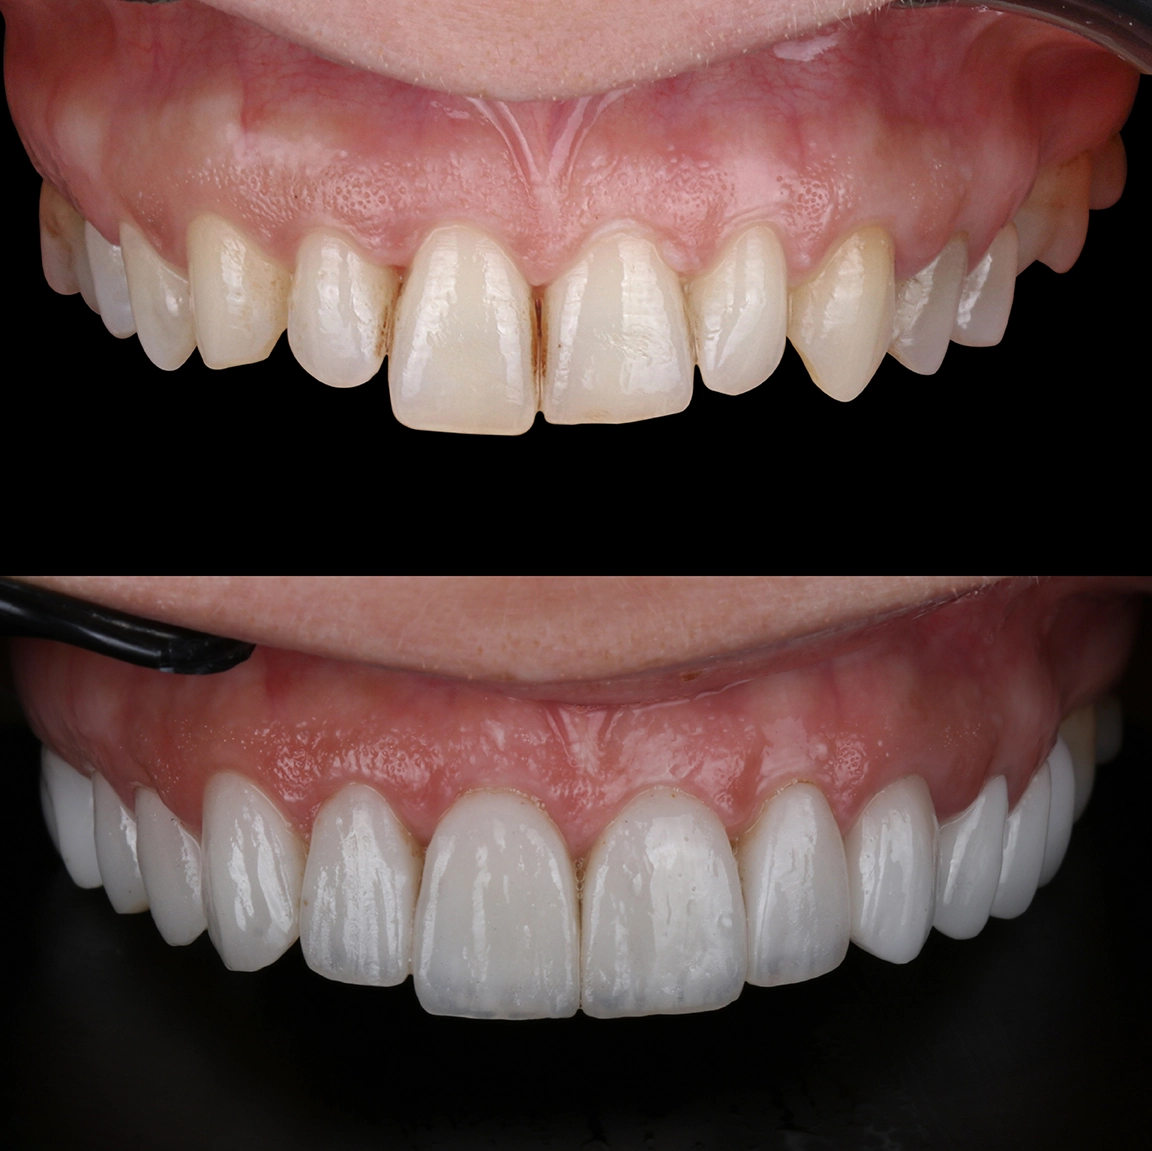

Risultati